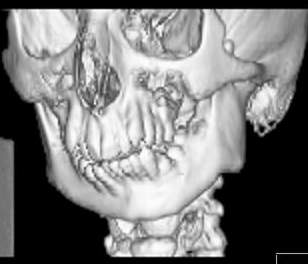

Пациент В., 13 лет. Диагноз: Костный анкилоз левого височно-нижнечелюстного сустава (ВНЧС), левосторонняя микрогения. Болеет с 2-х летнего возраста. Возможная причина развития анкилоза – воспалительный процесс (в первые 1,5 года жизни часто болел простудными заболеваниями, травму родители отрицают). В 3 и 5 лет проводилась редрессация – безуспешно.Прилагаются: ортопантомограмма, кадры СКТ с 3Д реконструкцией. Вопросы: определение тактики лечения – вид и сроки реконструктивно-пластической операции (этапов операции), а именно – неоартропластики и устранения микрогении, медикаментозная терапия в до- и послеоперационный период, ортодонтическое лечение.